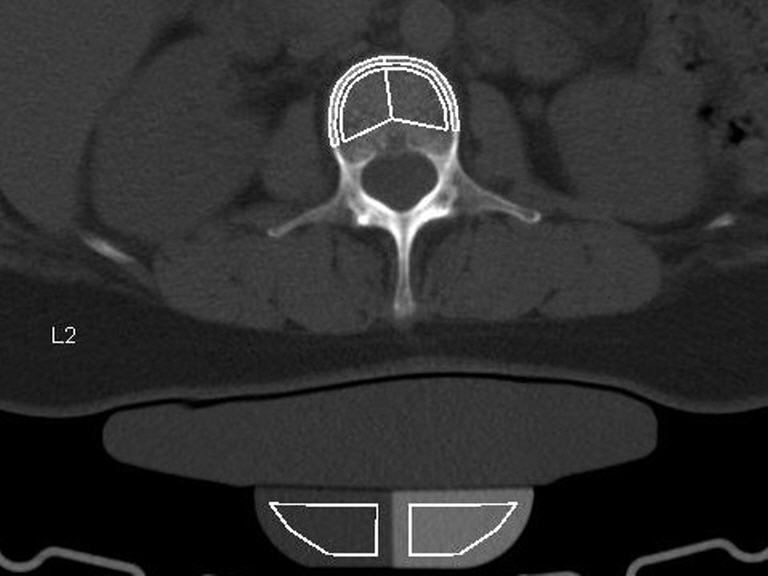

Knochendichtemessung mittels QCT

Unterstützen Sie Ihre Knochengesundheit mit einer Knochendichtemessung mittels QCT (Quantitative Computertomographie). Diese moderne Untersuchung bietet eine genaue und zuverlässige Messung der Knochendichte, sodass Osteoporose bereits in einem frühen Stadium erkannt werden kann. Besonders postmenopausale Frauen und ältere Menschen sind von Osteoporose betroffen – eine häufige Erkrankung, die das Risiko von Knochenbrüchen erheblich erhöht. Mit der QCT können wir gezielt und präzise Veränderungen der Knochendichte messen und frühzeitig handeln.